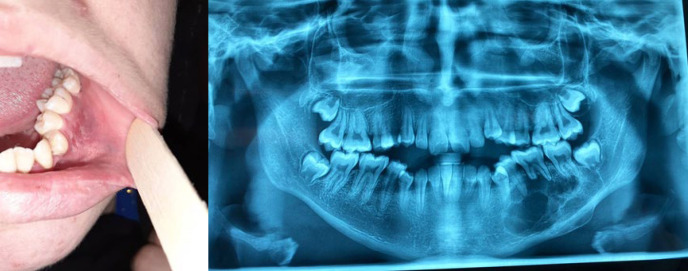

中央巨细胞肉芽肿(CGCG)是颌面部病理学领域中一种罕见但临床意义重大的疾病。本文介绍了一例令人信服的 17 岁女性中央巨细胞肉芽肿病例,揭示了该病在诊断和治疗方面遇到的挑战。鉴于 CGCG 在这一人群中的发病率相对较低,该病例不仅有助于临床对 CGCG 的理解,而且还强调了为患者量身定制特定管理策略的重要性。通过本报告,我们旨在阐明 CGCG 在表现、诊断和治疗方面的复杂性,同时强调在处理青少年患者的这一病症时必须考虑的细微因素。

The occurrence of Central Giant Cell Granuloma (CGCG) represents a rare yet clinically significant entity within the realm of maxillofacial pathology. This article presents a compelling case of CGCG in a 17-year-old female, shedding light on the diagnostic and therapeutic challenges encountered in managing this condition. Given the relative infrequency of CGCG in this demographic, the case not only contributes to the clinical understanding of CGCG but also underscores the importance of tailored, patient-specific management strategies. Through this presentation, we aim to elucidate the intricacies of CGCG manifestation, diagnosis, and treatment while highlighting the nuanced considerations essential in addressing this pathology in adolescent patients.